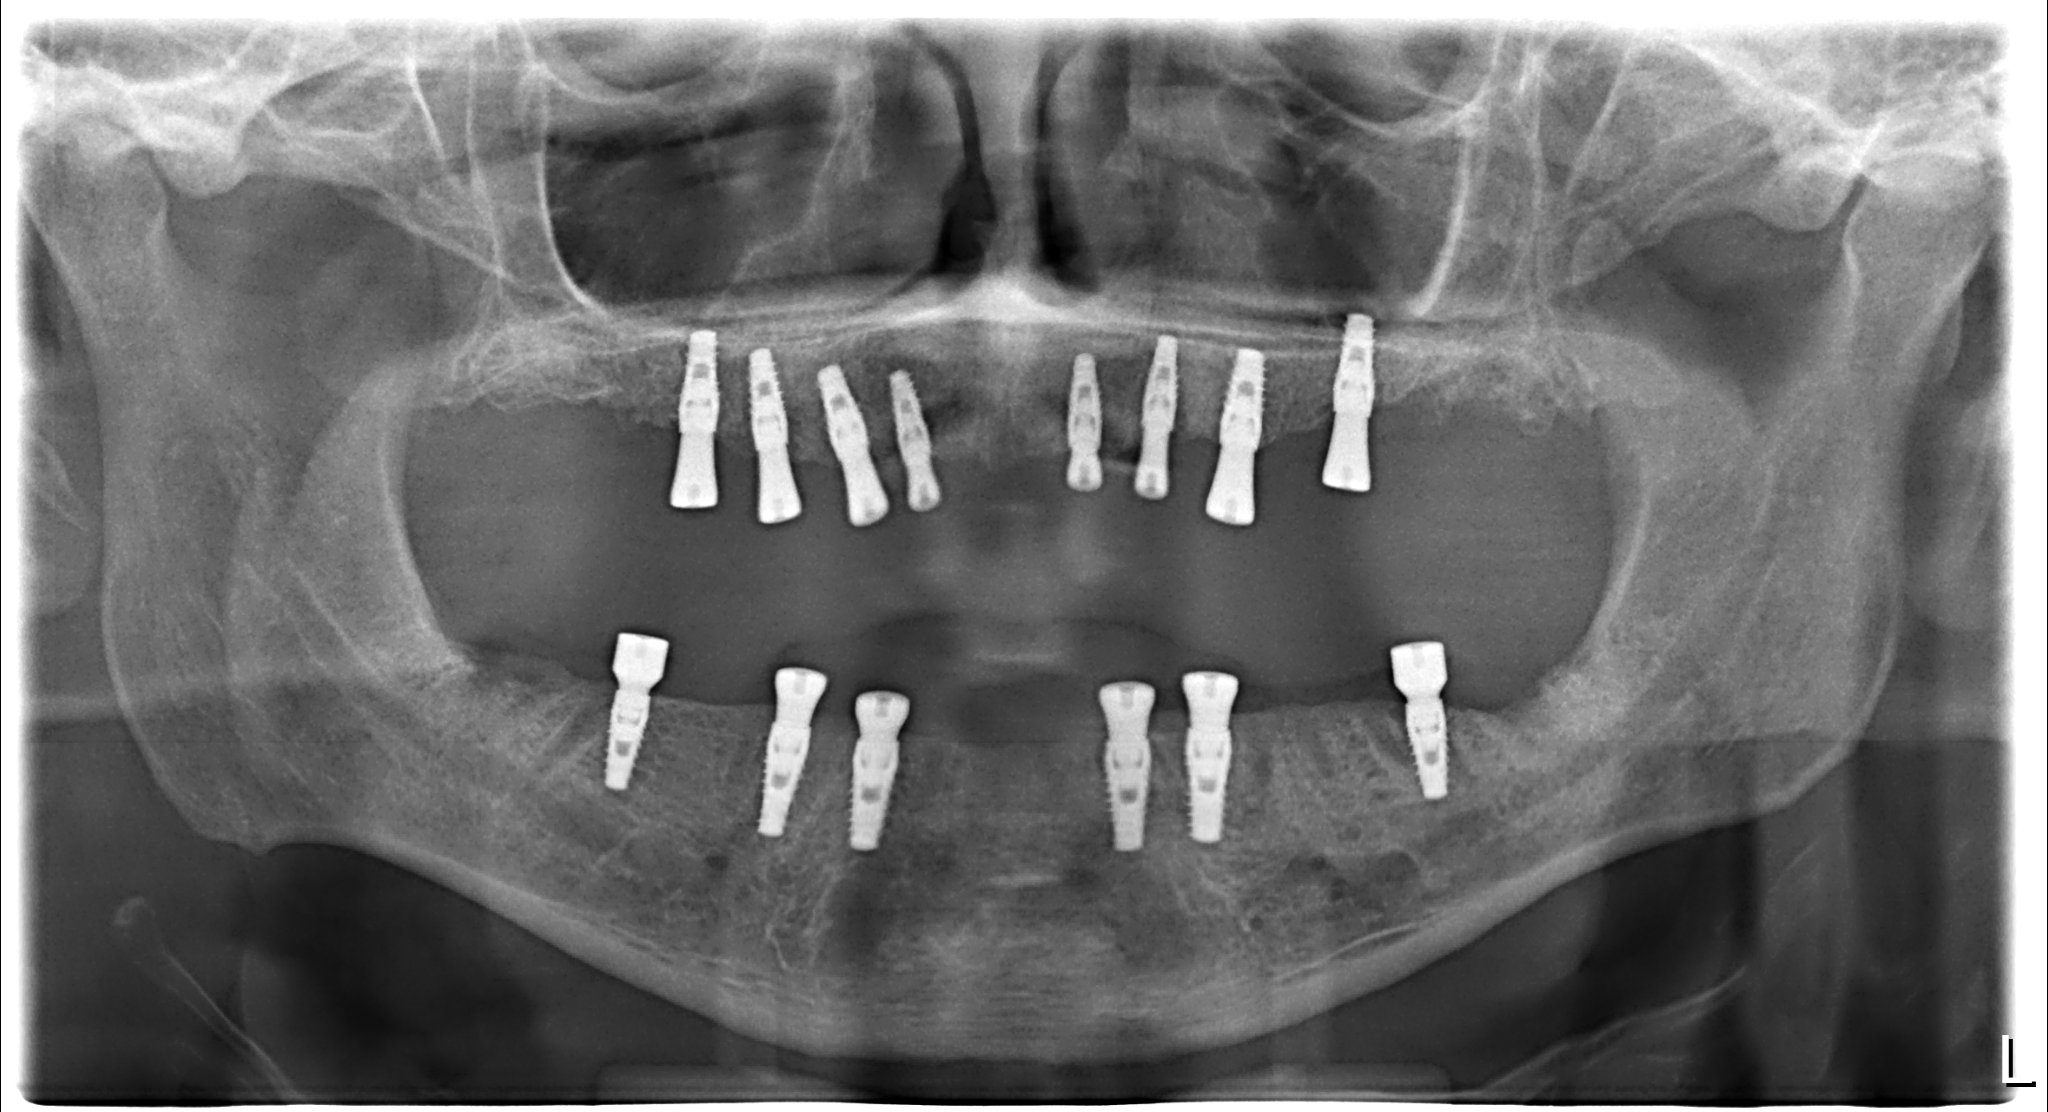

Six Naxis implants were successfully placed in the lower jaw, while eight were placed in the upper jaw. Following implant surgery, immediate healing abutments were used to expedite recovery and reduce the risk of infection.

Three months later, after the completion of implant osseointegration, the patient's need for prostheses was evaluated. Zirconium prostheses were preferred to meet the patient's aesthetic and functional requirements. Zirconium prostheses offer advantages in terms of durability and natural appearance.